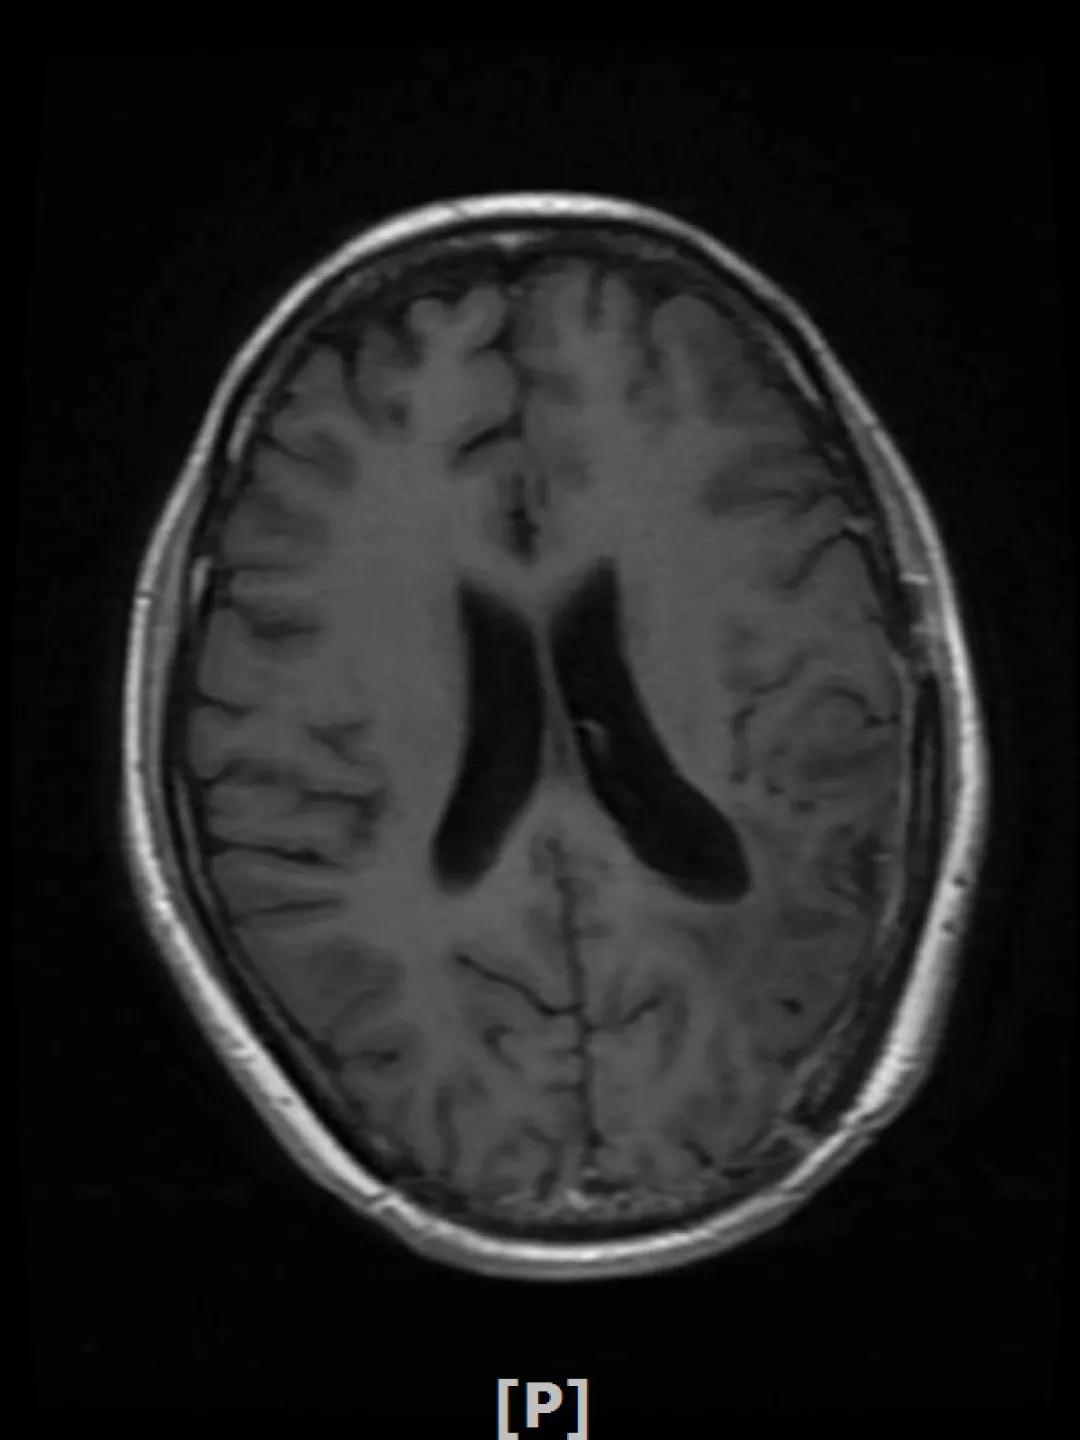

b.2014年3月全脑放疗结束后,予以LX方案治疗(拉帕替尼 1250mg qd+卡培他滨 1500mg bid)。每3个月规律复查,未见明显异常。下图为2014年6月患者行头颅增强MR检查,提示左顶叶脑转移瘤术后改变。

每3个月规律复查,未见明显异常。如2015年8月 头颅MR检查,提示:左顶叶脑转移瘤术后放疗后改变,对比前片2015年3月10日相仿。